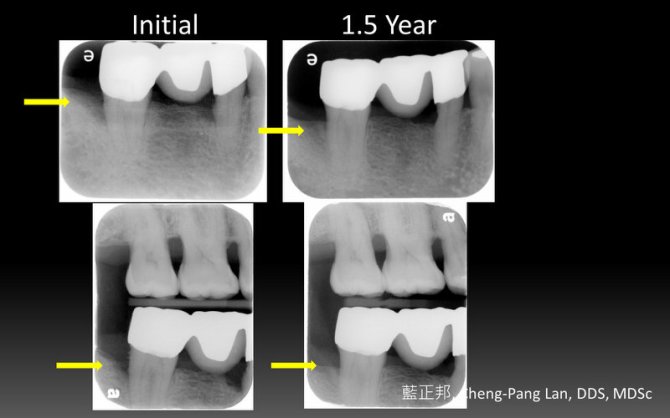

Guided Tissue Regeneration – Case B

This entry was posted in Periodontal Regeneration and tagged Autogenous bone, GTR, Intrabony defect, PLA/PGA menbrane, Resective osseous surgery, Trap-door. Bookmark the permalink.